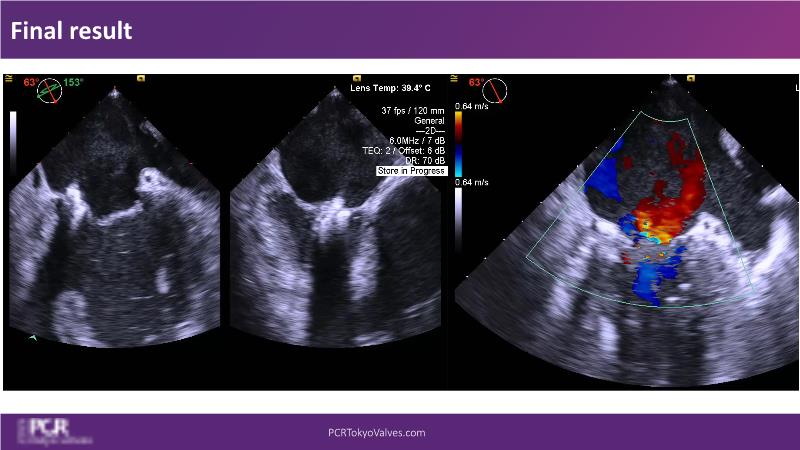

Watch this session to get an overview of a new TEER device, follow the step-by-step procedure related to initial experiences with this device for a Japanese patient with degenerative mitral regurgitation, learn about the latest data from RCT and registries, and follow discussions of challenging TEER cases!

- To learn procedural step-by-step of novel device